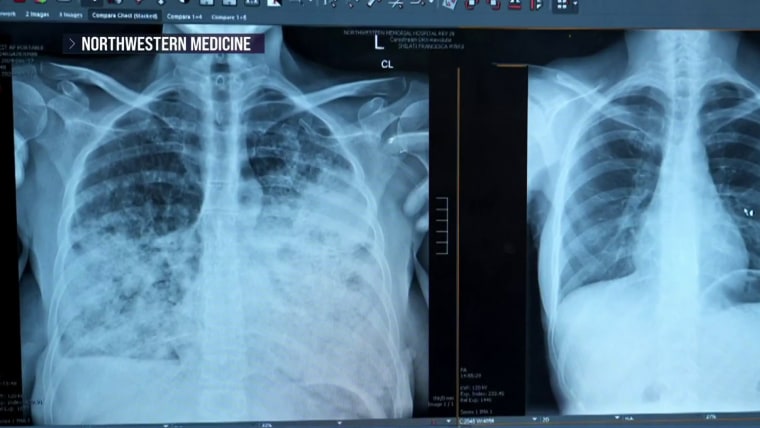

People still think of lung cancer as a disease that only affects older men and lifetime smokers, even though it’s becoming more common in younger women and people who never smoked, said lead study author Dr. Ankit Bharat, executive director of the Northwestern Medicine Canning Thoracic Institute in Chicago. “Every day, we are seeing patients who’ve never smoked, who may have had passive smoking exposure, they’re coming with advanced lung cancer, and then it’s not curable.”

Bharat’s research found that 65% of lung cancer patients at Northwestern didn’t qualify for screening based on the current guidelines. Women, Asian Americans and nonsmokers diagnosed with lung cancer were likelier to be ineligible for screening, the study found. (Another study, published Wednesday in the Journal of the American Medical Association, found that even among people eligible for screening, less than 20% were up to date.)

In Bharat’s study, researchers modeled how many cases they would’ve caught by expanding the screening criteria. If the guidelines included people who smoked a pack a day for 10 years and were ages 40 to 85, they could increase the detection rate to 62%. If they used a universal approach, screening all adults in that age group regardless of smoking status, they would’ve caught 94% of cancers.

“Having such a universal program would not only capture a majority of these patients, but we would be able to detect most of these patients at an earlier stage, which would dramatically improve the long-term survival as a whole population, with regards to lung cancer,” Bharat said.